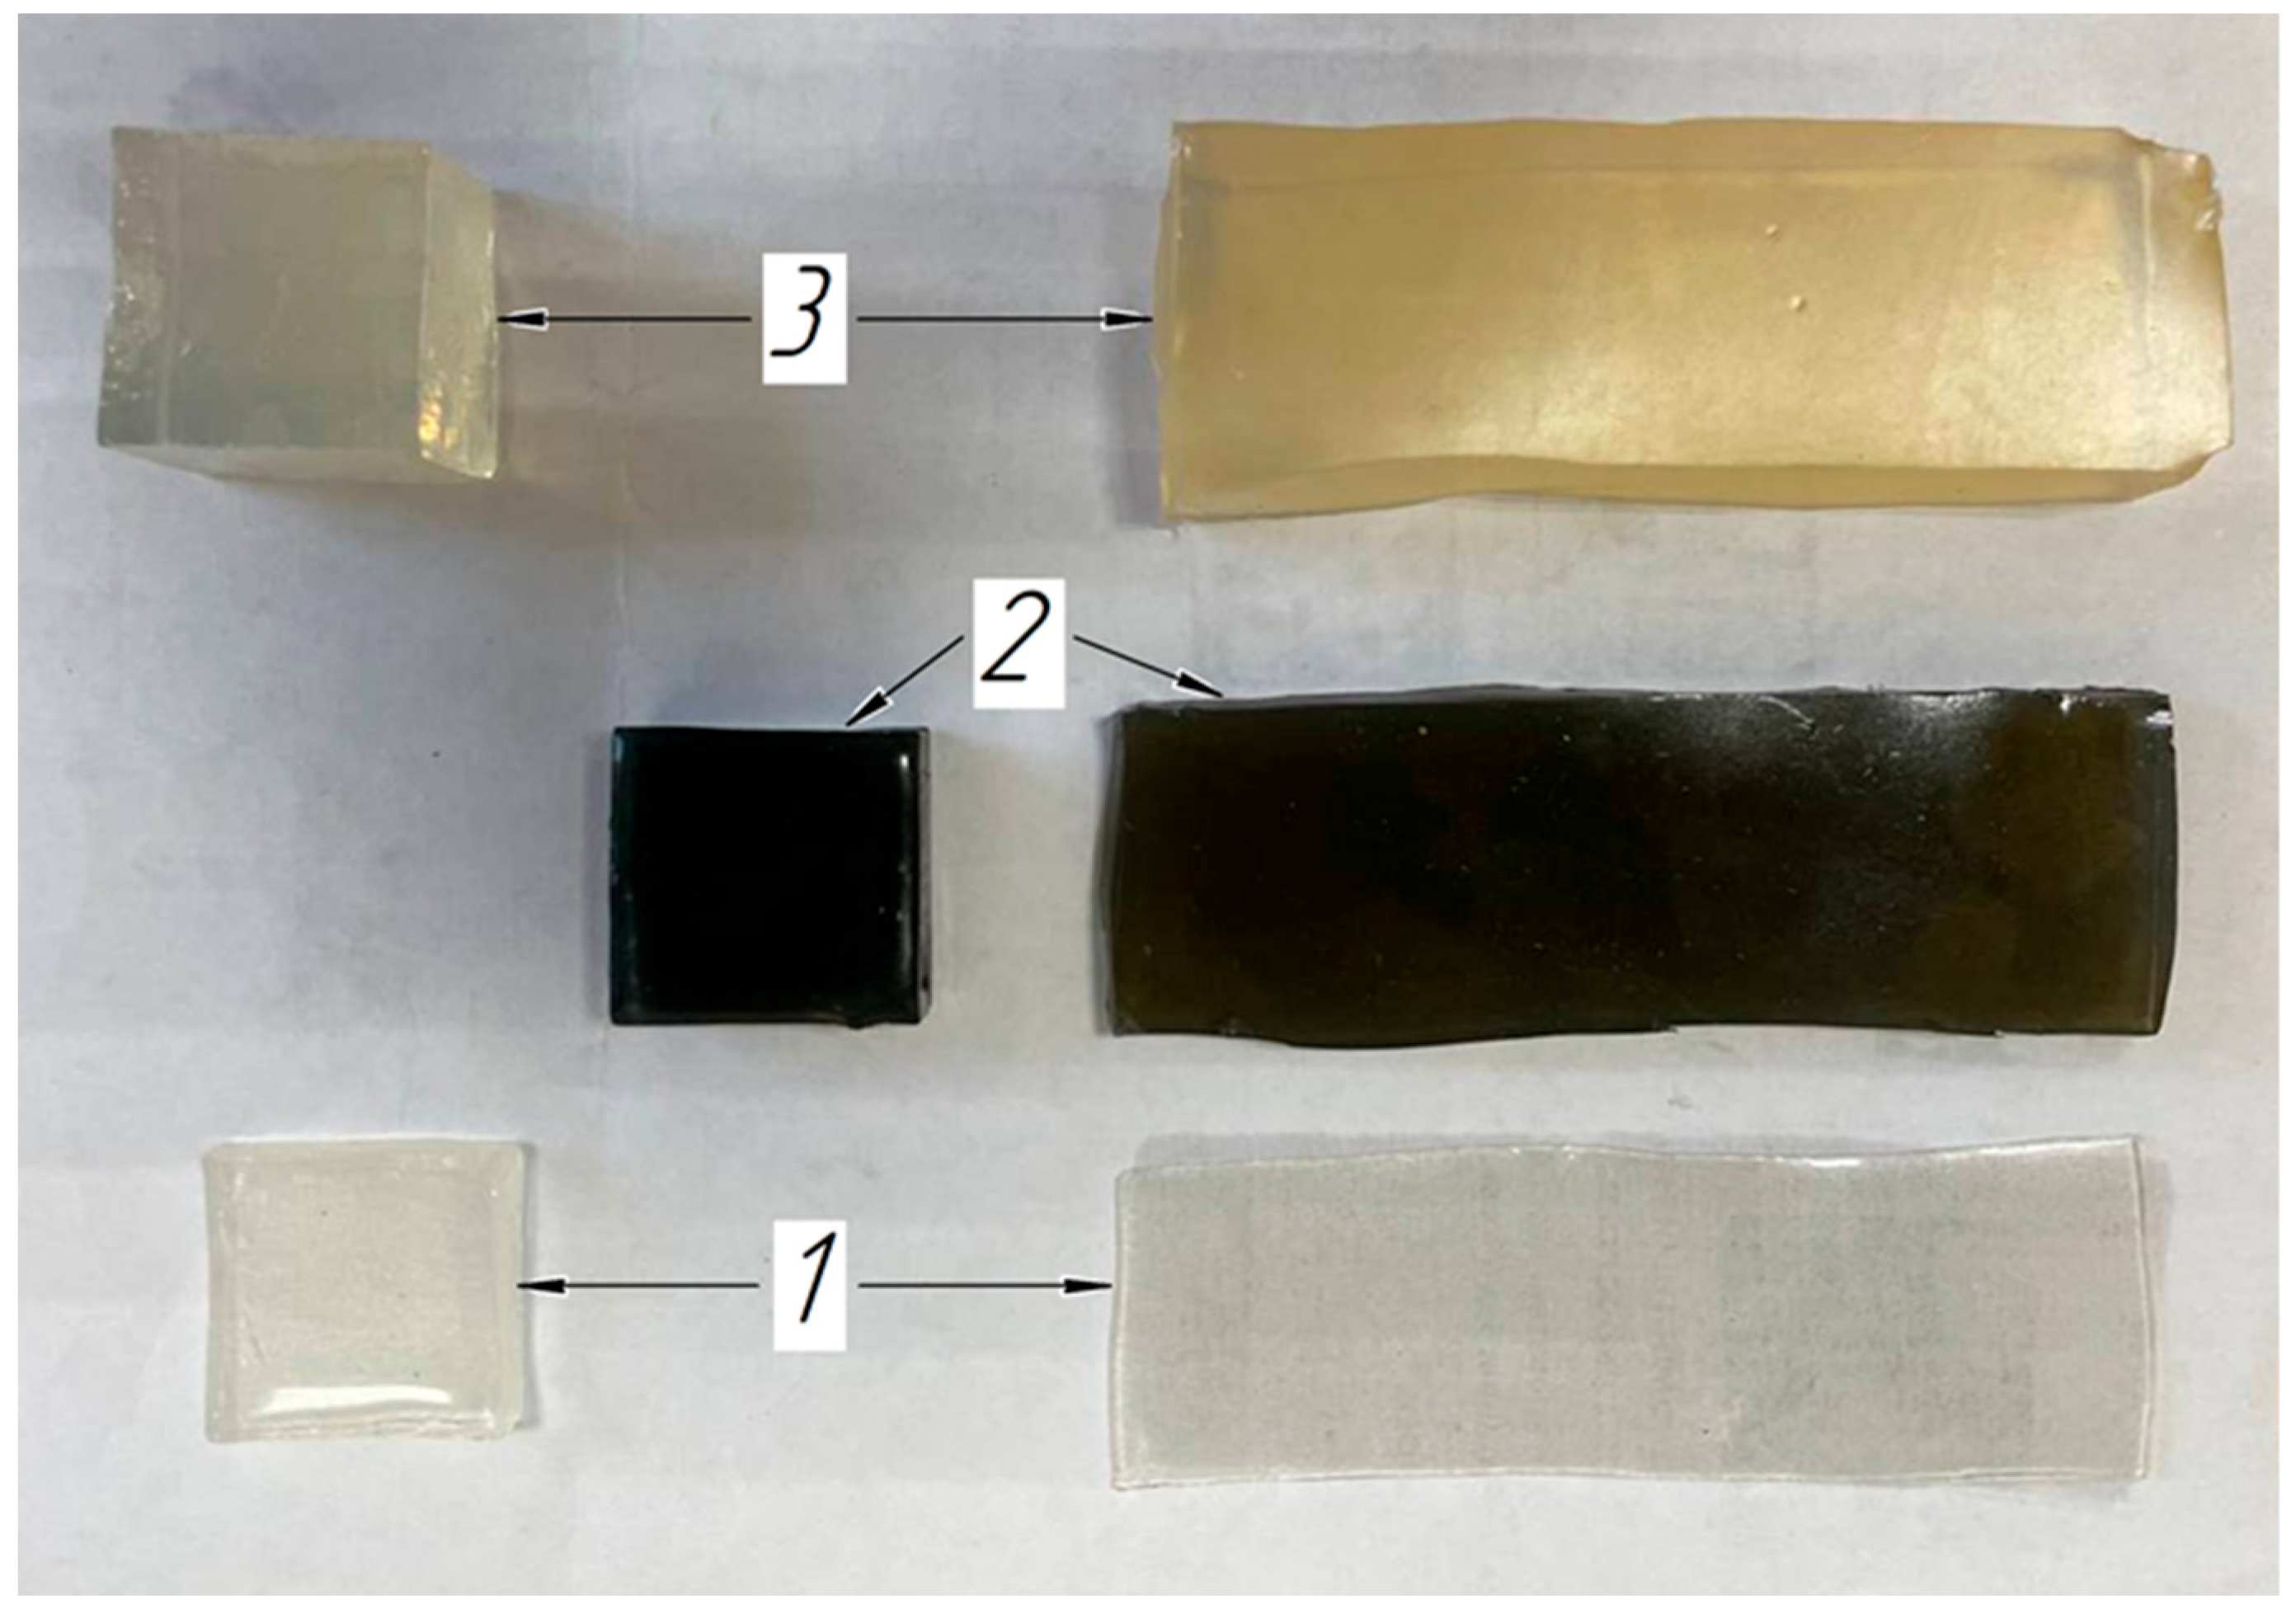

2.4. Soft Tissue Phantom Development

3.2. Verification of the Methodology for Constructing the Soft Tissue Volumetric Models